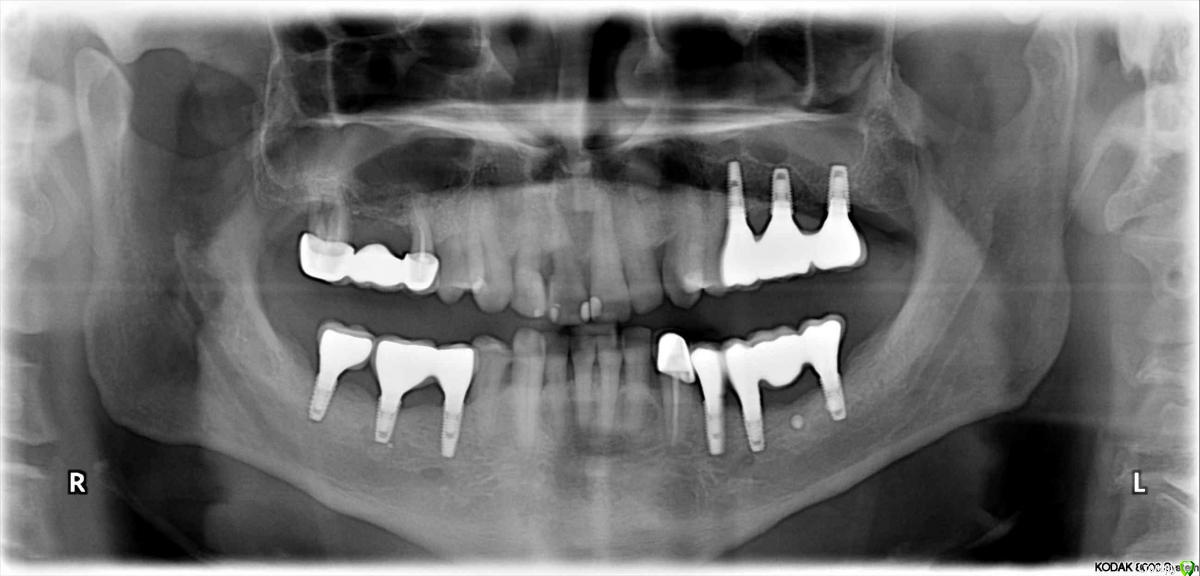

Это всё варианты платформ под кадкам. Вариобейс в штраумане, Линк в остеме и тд, и везде они короткие, по 1-3 мм,как думаете коллеги, зачем подобные платформы вообще вводят в линейку? Предположу, что склейка мультилинком в руках исключает риск попадания цемента, но всё же по современным концепциям, в т.ч. Зеро Лос концепт, такой профиль прорезывания не даст оптимальных резальтатов. Хотя тот же Томас линкевичус демонстрировал кейсы с подобным профилем и хорошими результатами, объясняя успех достаточным количеством кости и десны...

ну 3 мм так то не короткое основание, а в самый раз. Производители вообще сами долго не могли понять как надо делать, они только вешают лапшу о своих мега исследованиях, на самом деле они идут параллельно с нами с обычными врачами и слушают пару-тройку опинион-лидеров, которые и вносят изменения в системы ну и + еще смотрят друг на друга, что другие сделали и копируют друг друга.

зачем подобные платформы вообще вводят в линейку? Это пришло ещё с тех времён когда имплантация была двухэтапная,постановка крестальная,уровень десны 2мм, о мягких тканях никто не думал,главное чтобы имплант прижился. Помню ортопеды просили убирать «избыток» десны по гребню. Сейчас концепция поменялась,пришло понимание как реагируют ткани,появилось понятие биологическая ширина. Как отметил Олег Юрьевич ,производители отстали и не в курсе дела.